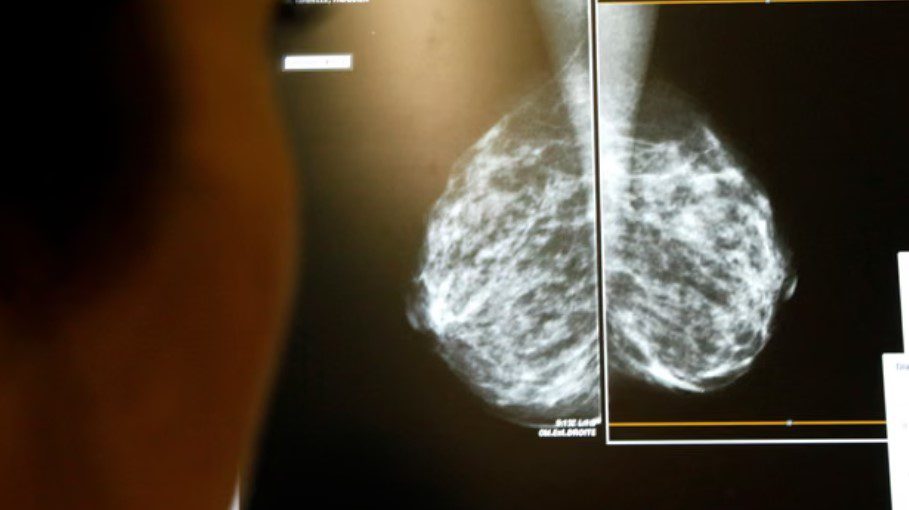

Përdorimi i inteligjencës artificiale (AI) në skanimet apo mamografitë për kancerin e gjirit ka ulur me 12 për qind rastet e diagnostikimit të vonshëm pas kontrollit fillestar, sipas një studimi të madh të realizuar në Suedi, ka raportuar The Guardian.

Studimi, i publikuar në revistën mjekësore The Lancet, ka përfshirë rreth 100 mijë gra që iu nënshtruan mamografisë mes viteve 2021 dhe 2022.

Gratë u ndanë rastësisht në dy grupe: një grup me mamografi të mbështetur nga AI dhe një grup me lexim standard nga dy radiologë.

Sistemi i inteligjencës artificiale analizonte imazhet e mamografisë, duke i ndarë rastet me rrezik të ulët për lexim nga një radiolog dhe ato me rrezik të lartë për lexim të dyfishtë, si dhe duke theksuar gjetjet e dyshimta për t’i ndihmuar mjekët.